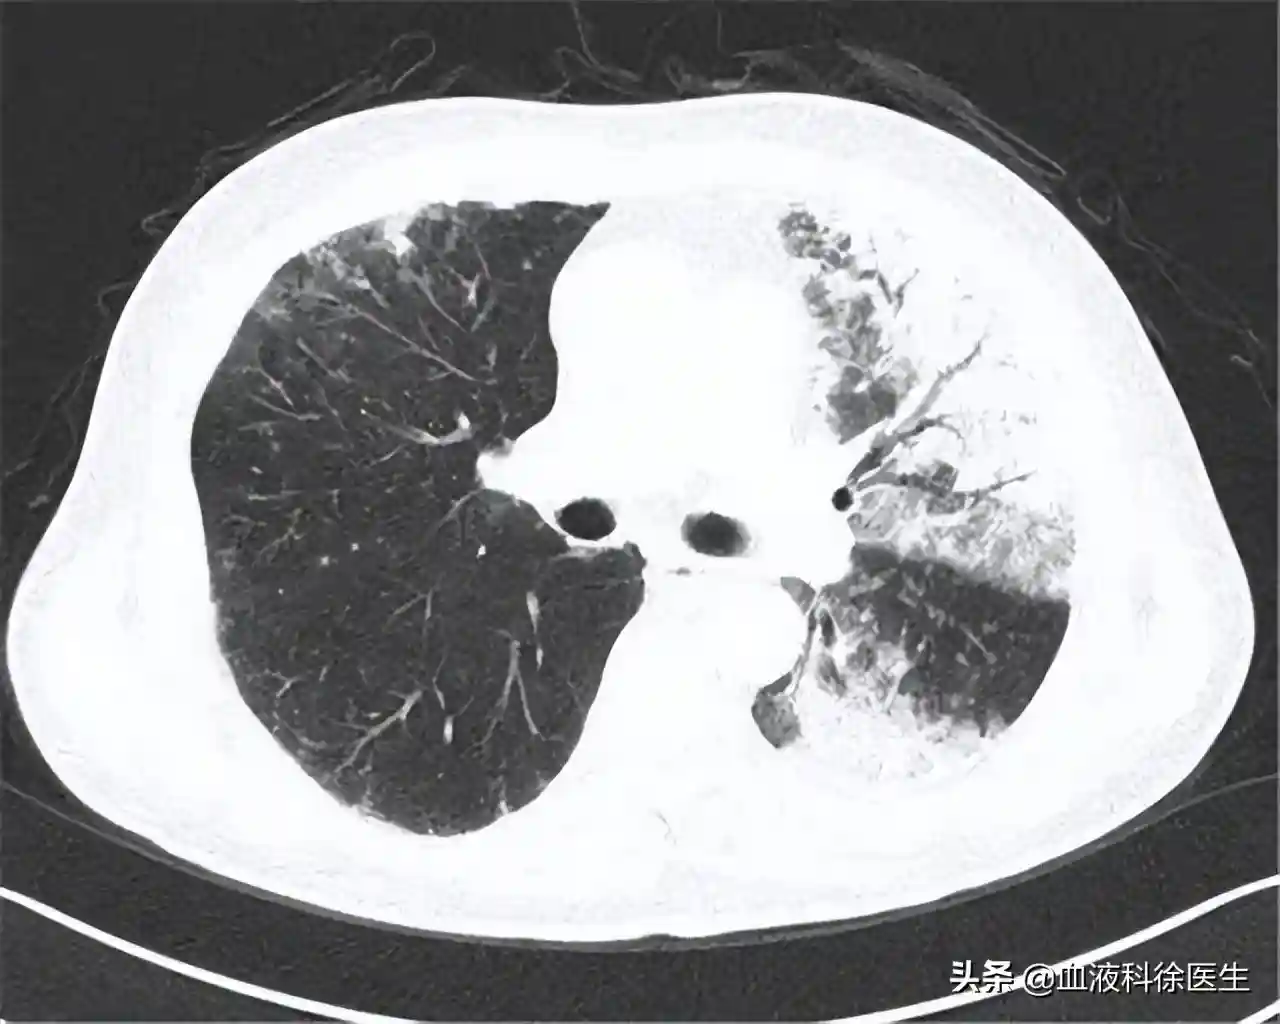

通过简单的胸部CT,右肺叶的主支气管上发现了硬币大小的病灶,为了进一步确定病灶是否是肿瘤,我们又给王叔做了胸部PEF-CT检查,通过深层的CT检查可以确定病灶形态为3cm×4cm×1.5cm恶性肿块,除了这一病灶外,支气管附近的肺叶上还分布着三个较小的肿块,表明肿块有肺内转移的情况。

通过支气管镜经呼吸道提取肿块组织,经过活检发现鳞状细胞癌,确诊为Ⅲb期非小细胞肺癌。